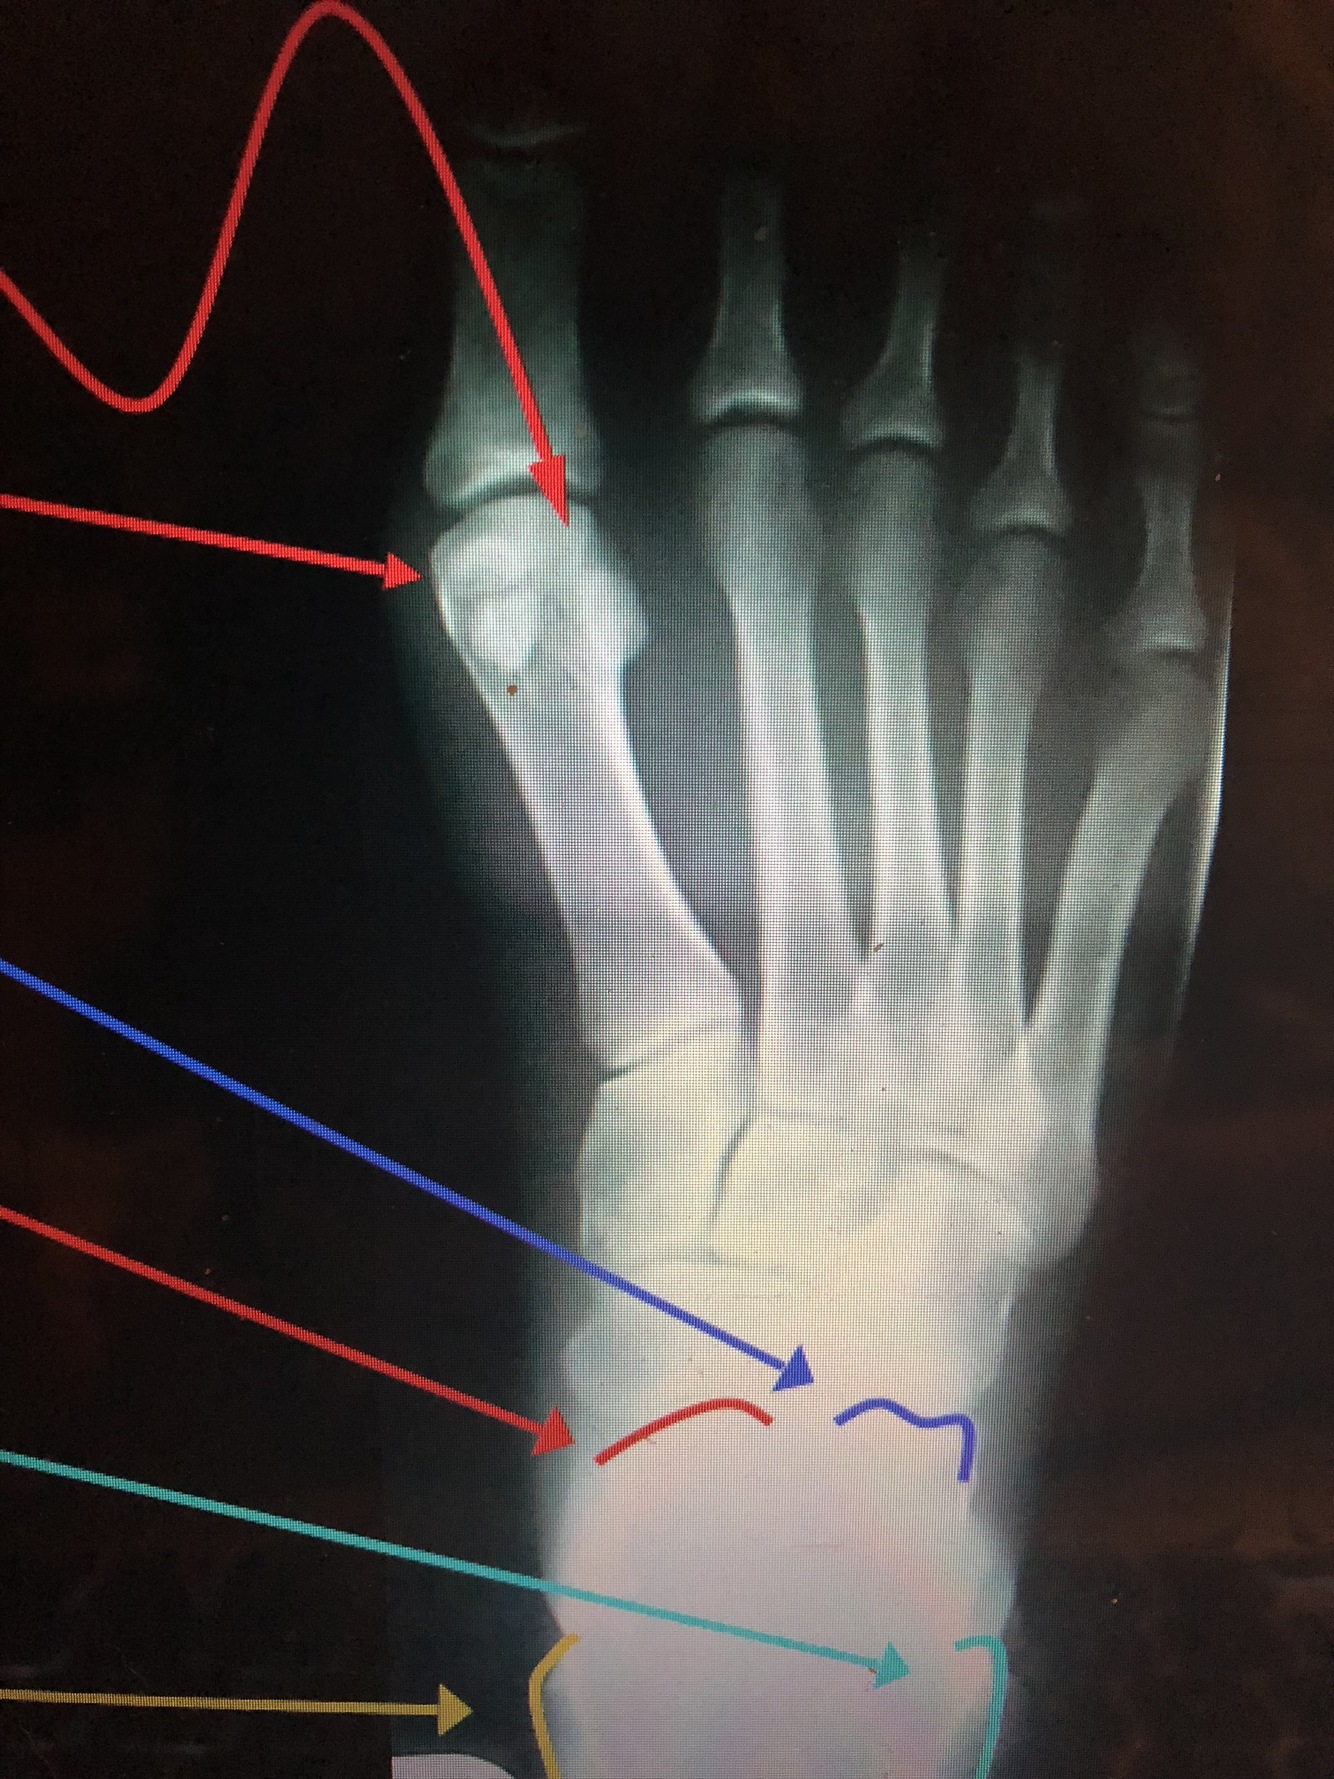

What are the top two red lines?

Sesamoid Bones

•Found in the tendon of the flexor hallucis brevis

What is the red line?

head of 1st metatarsal

What is the dark blue line?

Neck of 2nd metatarsal

What is the yellow line?

Shaft of 3rd metatarsal

What is the light blue line?

base of the 3rd metatarsal

Styloid Process of the 5th Metatarsal

• Common fracture site in an inversion ankle sprain due to the pull of the peroneus brevis muscle